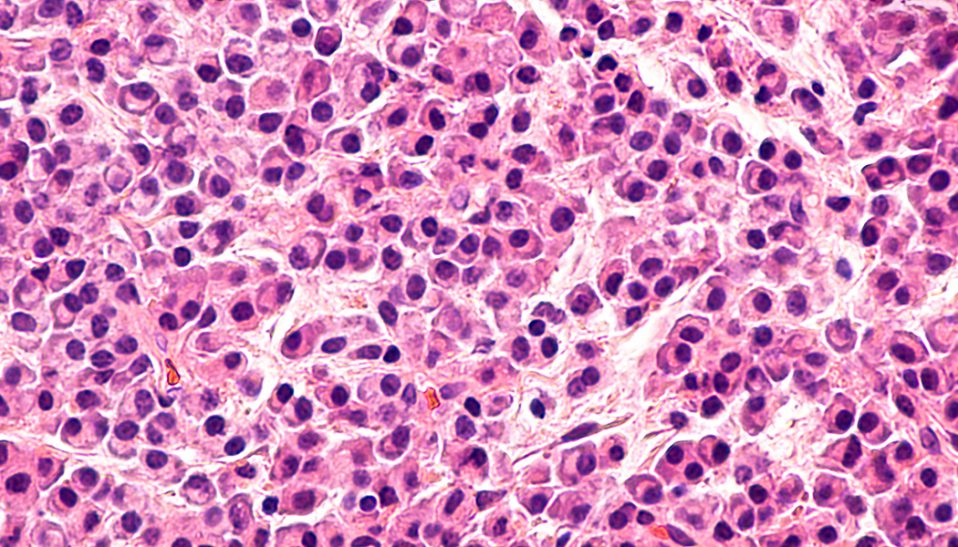

It is the “new territory” of oncology: Getting the immune system to successfully fight a standing cancer. No other biological system within our bodies is more suited, adept or evolved to such a purpose. Indeed, our immune system is remarkably successful in spotting and destroying the tiny genetic mutations from…...